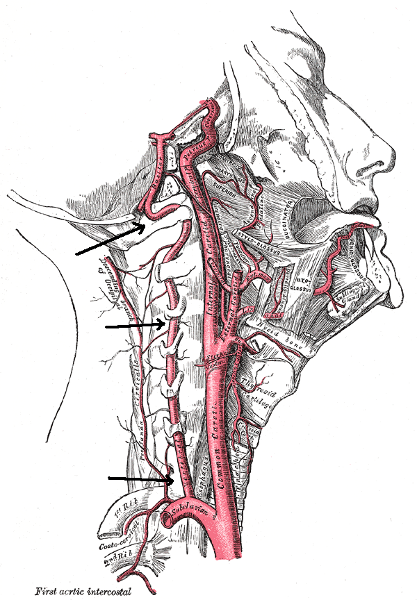

Internal/external/common carotid artery

internal/external/common jugular vein

Basilar artery

Brachiocephalic artery

Brachiocephalic vein

Subclavian artery/vein

Vertebral artery